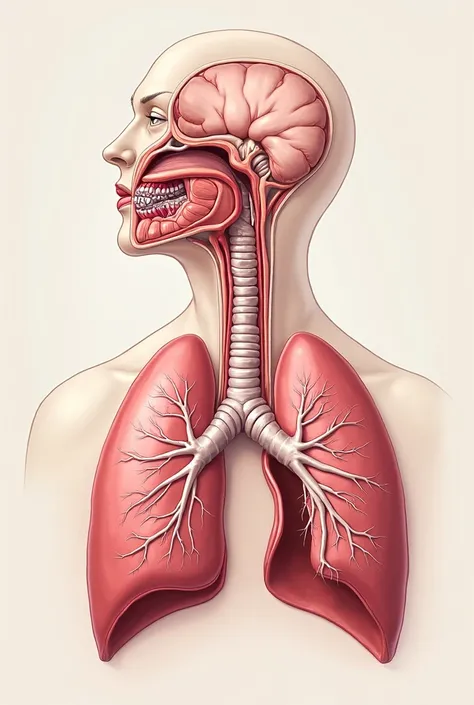

Make a folder about bacterial pneumonia

Make a folder about bacterial pneumonia

Make a folder about bacterial pneumonia